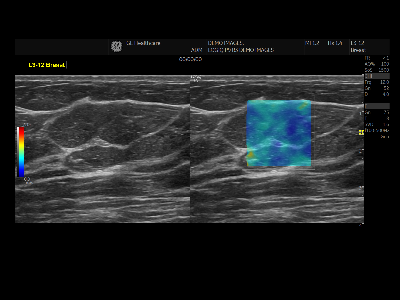

Ultrasonography : エコー検査

超音波(エコー)という人の耳には聞こえない音波を体表に当て、体内の組織から跳ね返ってきたエコーを画像にする検査です。

高濃度乳房の方はマンモグラフィでは病気が見つけにくいことがあります。エコーと併せて評価をお勧めします。